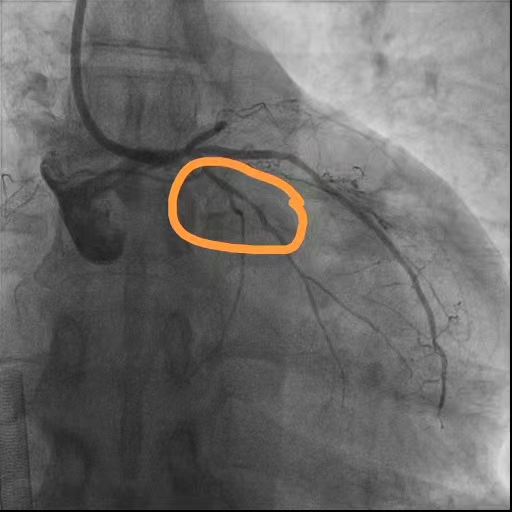

术前

回旋支狭窄

前降支近段闭塞